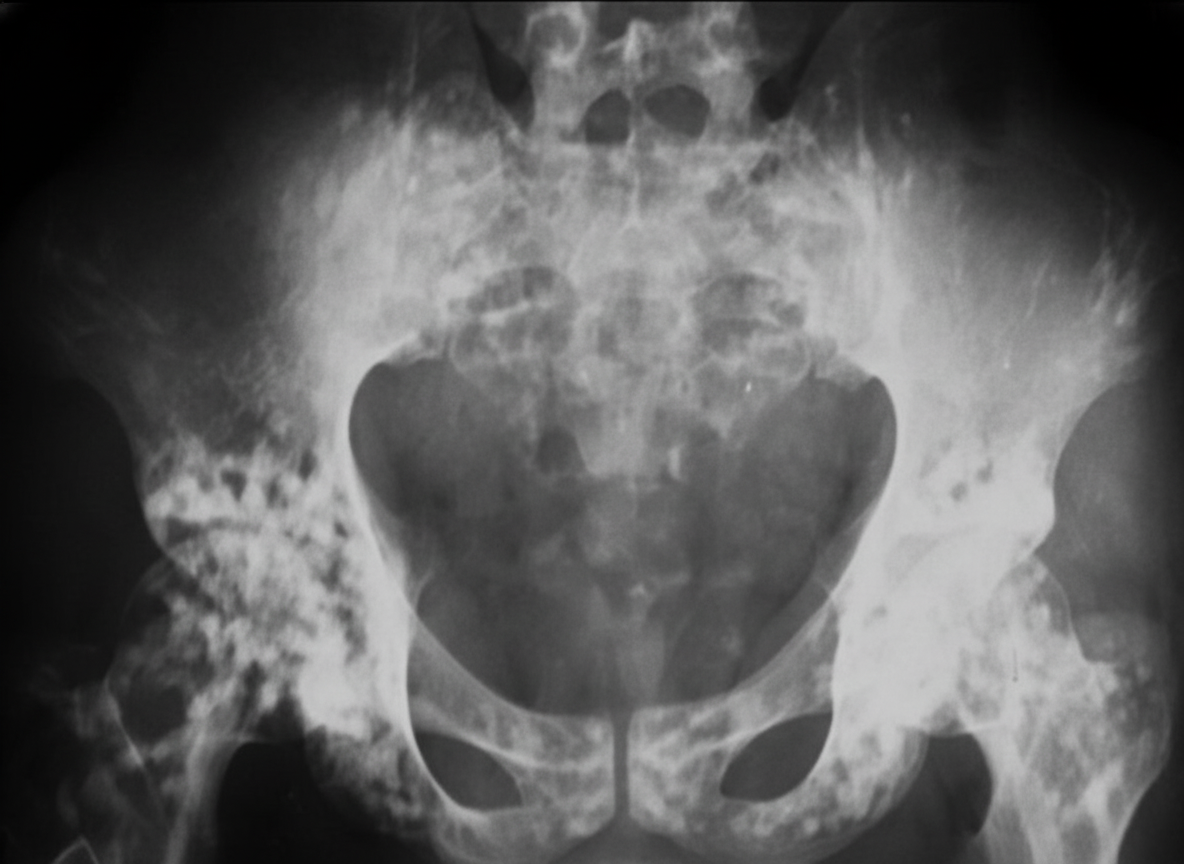

Explanation: ***Achondroplasia*** - Characterized by **rhizomelic shortening** (proximal limb shortening) and classic **trident hand** deformity with hand and pelvic abnormalities. - X-ray features include **champagne-glass pelvis**, **small squared iliac wings**, **horizontal acetabular roof**, and **narrow sacroiliac notch**. *Rickets* - Primarily causes **metaphyseal** changes with **widening**, **cupping**, and **fraying** of bone ends, not specific hand deformities. - Characterized by **bowing deformities** of weight-bearing bones and **delayed epiphyseal ossification**, but lacks trident hand pattern. *Osteogenesis imperfecta* - Presents with **multiple fractures** with minimal trauma and **blue sclerae** as hallmark features. - Bone deformities result from **recurrent fractures** rather than specific developmental abnormalities of hands and pelvis. *Cushing syndrome* - Causes **centripetal obesity**, **moon facies**, and **purple striae** rather than skeletal deformities. - Growth retardation occurs due to **cortisol excess** affecting growth hormone, not structural bone abnormalities.

Explanation: In Perthes' disease (Legg-Calvé-Perthes), the prognosis depends heavily on the degree of femoral head involvement and its containment within the acetabulum. To predict outcomes, Catterall described specific radiological features known as **"Head-at-Risk" signs**. ### Why "Shallow Acetabulum" is the Correct Answer A **shallow acetabulum** is not a "Head-at-Risk" sign. In fact, Perthes' disease often leads to a secondary *deepening* or remodeling of the acetabulum to accommodate a flattened femoral head (coxa plana). While acetabular dysplasia is a primary feature of Developmental Dysplasia of the Hip (DDH), it is not a prognostic marker for Perthes'. ### Explanation of "Head-at-Risk" Signs (Incorrect Options) The following signs correlate **positively with a poor outcome** (increased risk of femoral head collapse and permanent deformity): * **Lateral subluxation of the femoral head (Option A):** Indicates the head is moving out of the protective cover of the acetabulum, leading to eccentric loading. * **Speckled calcification lateral to the epiphysis (Option B):** Represents calcification in the cartilaginous part of the head outside the acetabulum, signifying severe extrusion. * **Gage sign (Option D):** A V-shaped radiolucency on the lateral side of the epiphysis/metaphysis. It indicates osteolysis and impending collapse of the lateral pillar. * *Other signs include:* Horizontal growth plate and diffuse metaphyseal reactions. ### NEET-PG High-Yield Pearls * **Age of Onset:** Most common in boys aged 4–8 years. * **Pathology:** Avascular necrosis of the proximal femoral epiphysis. * **Classification Systems:** * **Catterall:** Based on the extent of necrosis. * **Herring (Lateral Pillar):** Most widely used for prognosis (Group A, B, and C based on the height of the lateral 1/3rd of the epiphysis). * **Management Goal:** "Containment" of the femoral head within the acetabulum using braces or osteotomy.